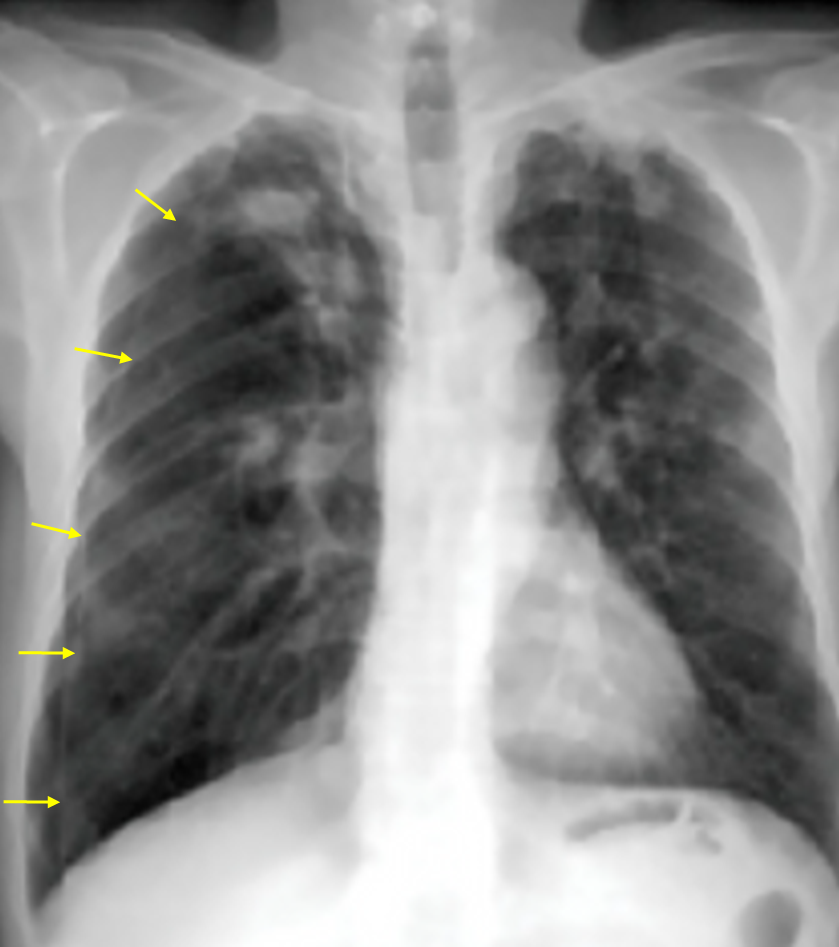

72세 남자가 하루 전부터 숨이 찬다며 병원에 왔다. 평소에는 평지를 걸을 때 숨이 찬 정도였으나 어제부터는 일상생활을 하기 어려울 정도로 숨이 차다고 하였다. 20년 전에 폐결핵을 앓았으며 50갑·년의 흡연력이 있다. 혈압 140/90mmHg, 맥박 102회/분, 호흡 24회/분, 체온 36.6℃이다. 청진할 때 오른쪽 가슴에서 호흡음이 작게 들린다. 가슴 X선 사진이다. 대기 호흡상태의 동맥혈가스분석 결과는 다음과 같다. 치료는?

Img | CXR : 우측 폐 pleural line |

• CXR에서 우측 폐에 pleural line이 보이며 distal vascular marking의 소실이 확인되므로 기흉으로 진단할 수 있다.